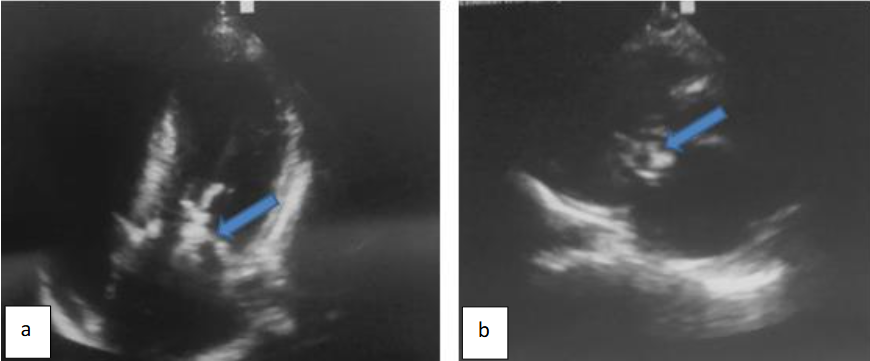

Furthermore, a voluminous mobile vegetation measuring 40 mm in long axis was seen mutilating the mitral valve anterior leaflet and prolapsing into the left auricle which was dilated, as shown in Figure 3.

Pulsed doppler detected marked mitral valve regurgitation as depicted in Figure 4.